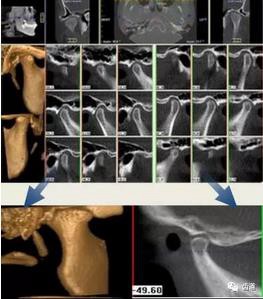

3、顳下頜關(guān)節(jié)

顳下頜關(guān)節(jié)CBCT影像